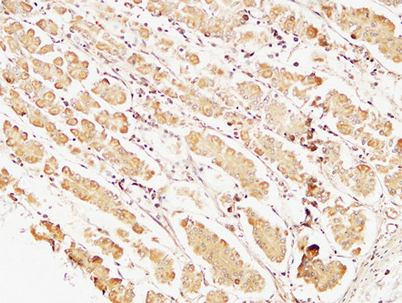

Caspase-7 rabbit pAb

Product name: Caspase-7 rabbit pAb

Reactivity: Human;Rat;Mouse;

Alternative Names: CASP7; MCH3; Caspase-7; CASP-7; Apoptotic protease Mch-3; CMH-1; ICE-like apoptotic protease 3; ICE-LAP3

Dilutions: Western Blot: 1/500 - 1/2000.IHC-p:1:50-300 ELISA: 1/20000. Not yet tested in other applications.

Immunogen: The antiserum was produced against synthesized peptide derived from human Caspase-7. AA range:45-94

Cellular localization: Cytoplasm.

Background: This gene encodes a member of the cysteine-aspartic acid protease (caspase) family. Sequential activation of caspases plays a central role in the execution-phase of cell apoptosis. Caspases exist as inactive proenzymes which undergo proteolytic processing at conserved aspartic residues to produce two subunits, large and small, that dimerize to form the active enzyme. The precursor of the encoded protein is cleaved by caspase 3 and 10, is activated upon cell death stimuli and induces apoptosis. Alternatively spliced transcript variants encoding multiple isoforms have been observed for this gene. [provided by RefSeq, May 2012],